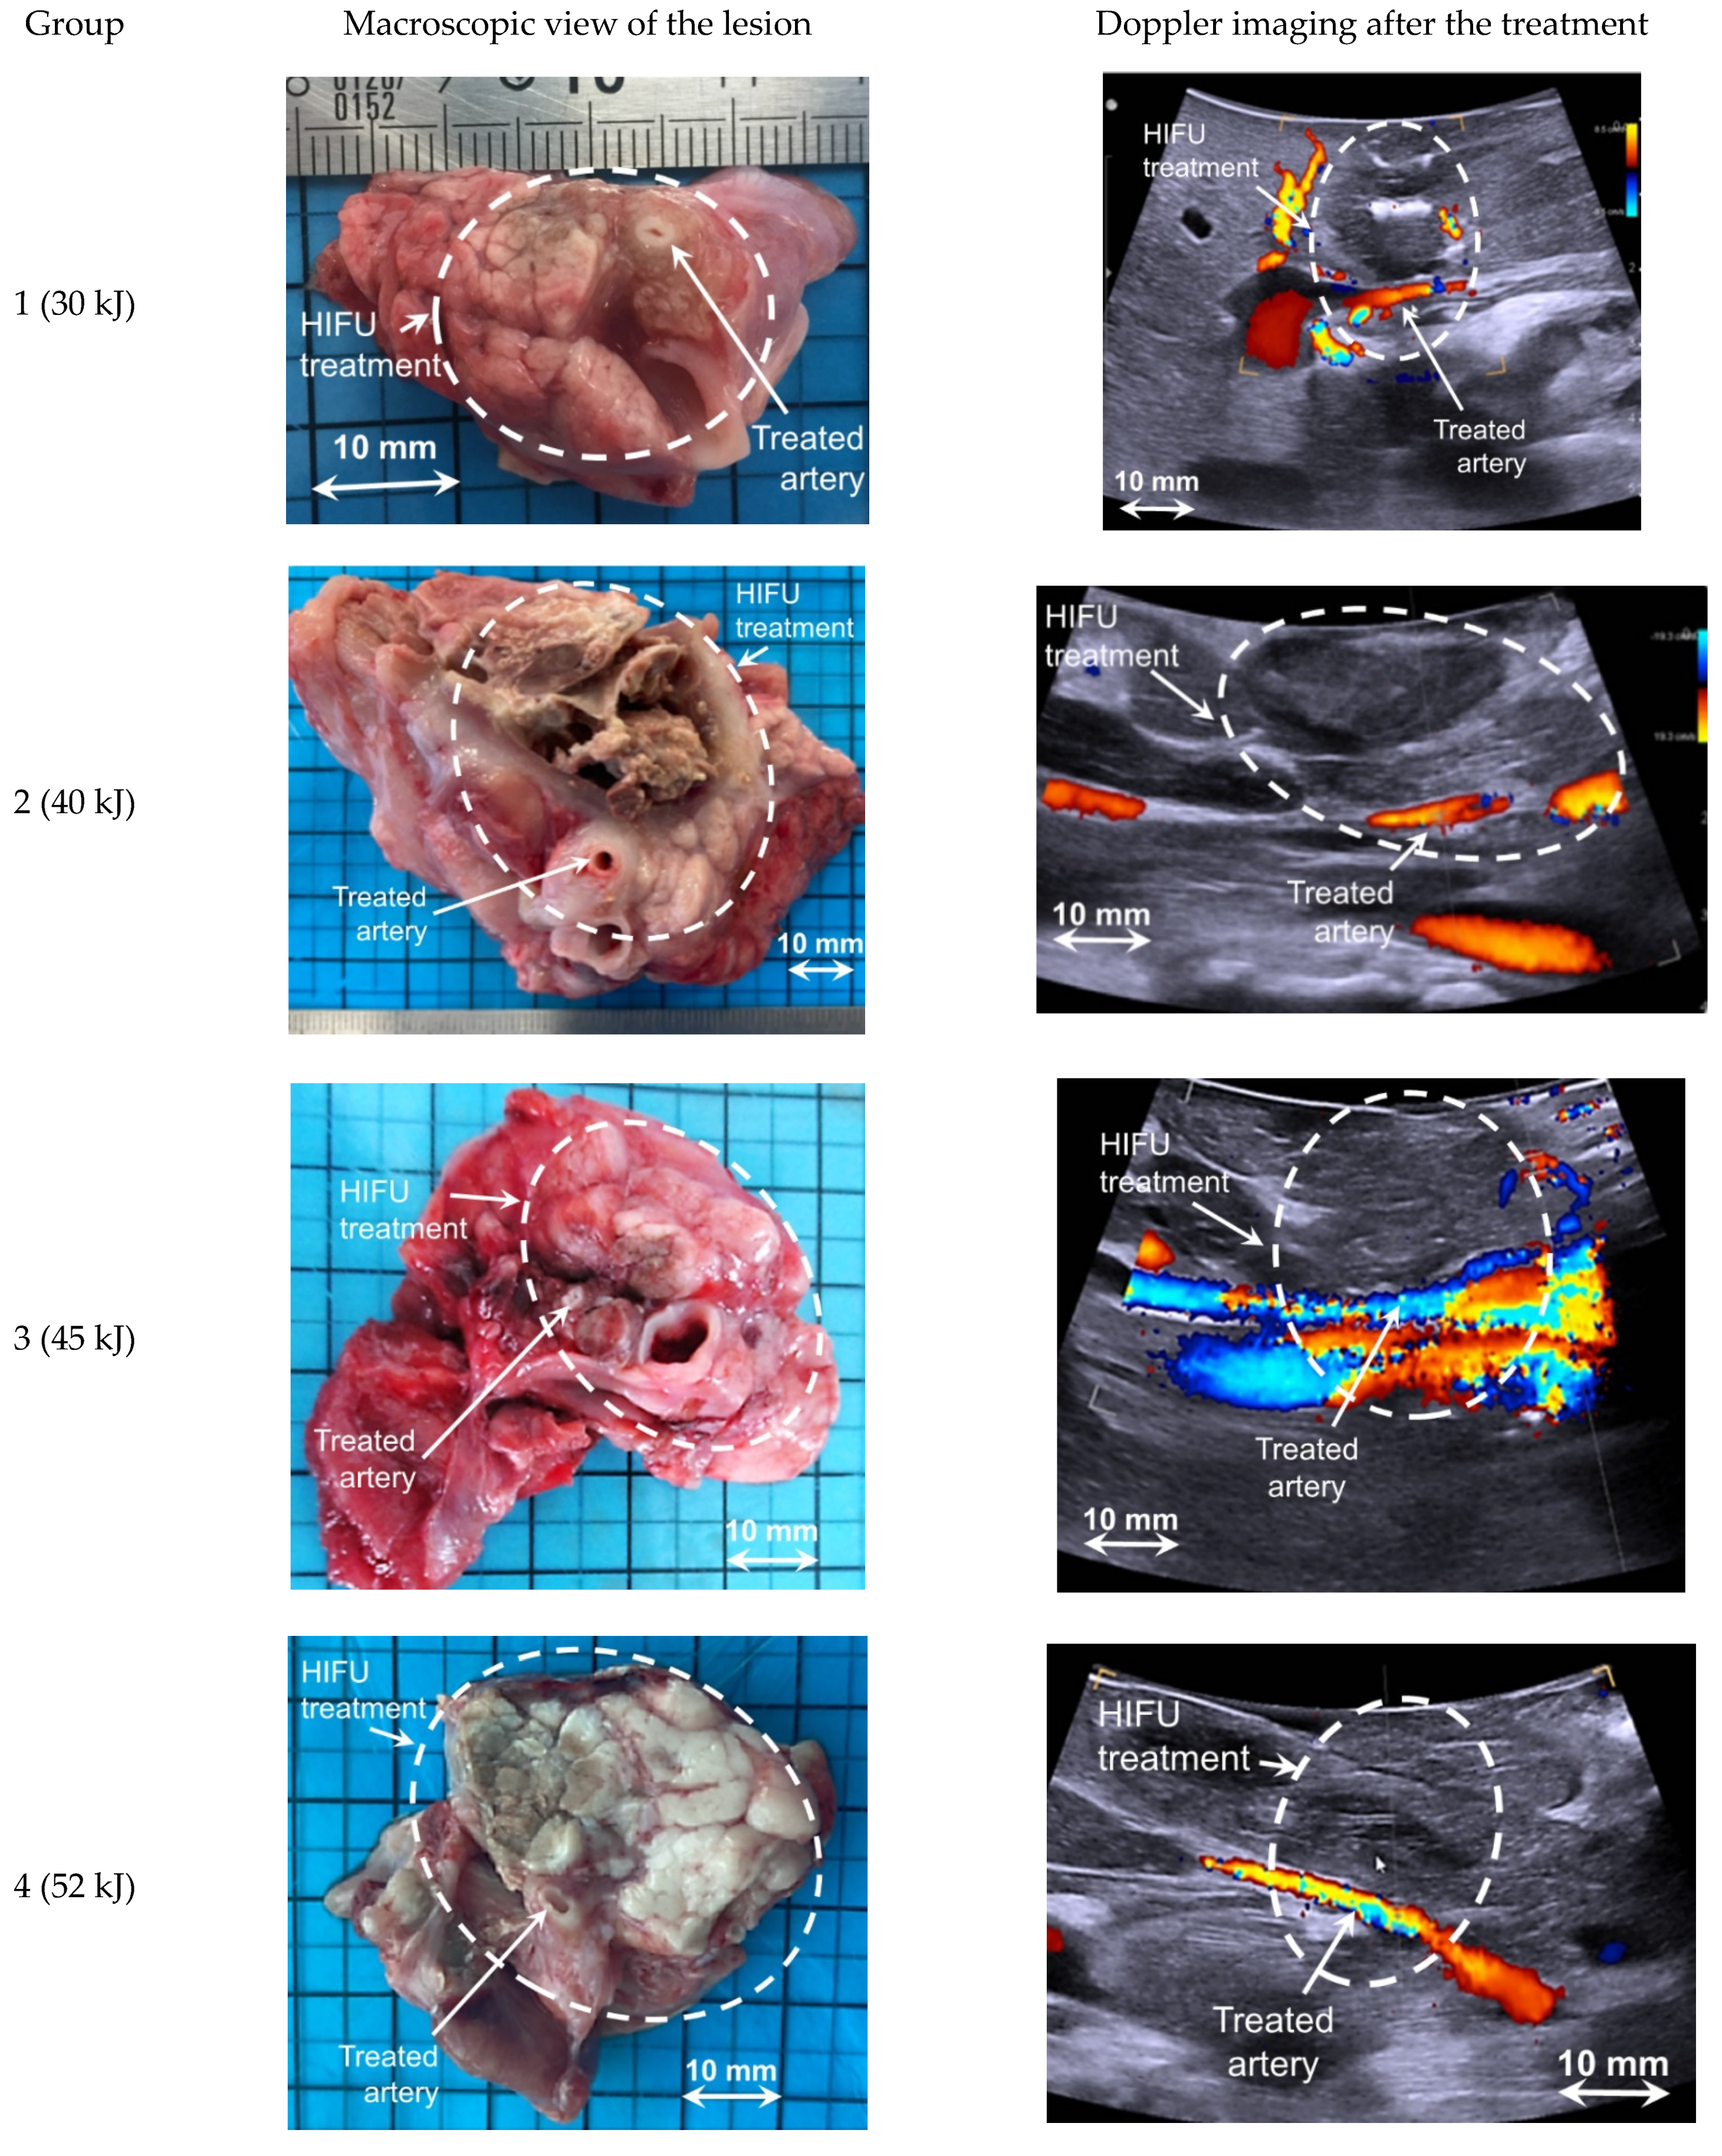

3.3. Analysis of HIFU Treatment